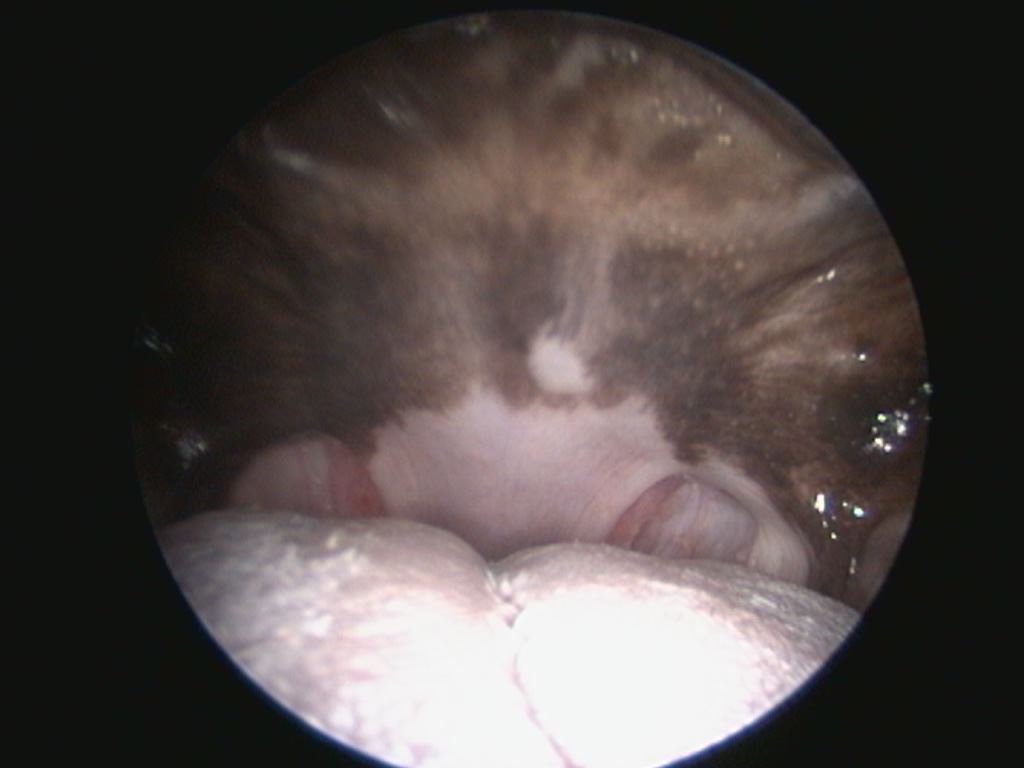

Jotain häämötti siellä pehmeän kitalaen takana:

Nenänielun alueella oli jumissa 9 cm pitkä heinä, joka poistettiin tähystyksen yhteydessä.

Heinä oli todennettavissa vain tähystyslaitteistolla nielusta taaksepäin eli nenäkuorikoihin päin tähystettäessä (kts. edellinen tähystyskuva).